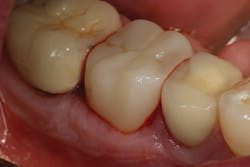

TheraCem exhibits minimal resistance to seating, but is not runny (figure 3). Cleanup is easy with hand instruments and floss (figure 4). For deeper subgingival margins, this cement is kind to the gingiva, although the margins should be thoroughly inspected to ensure complete removal of excess cement (figure 5).

Figure 5: Inspected margins